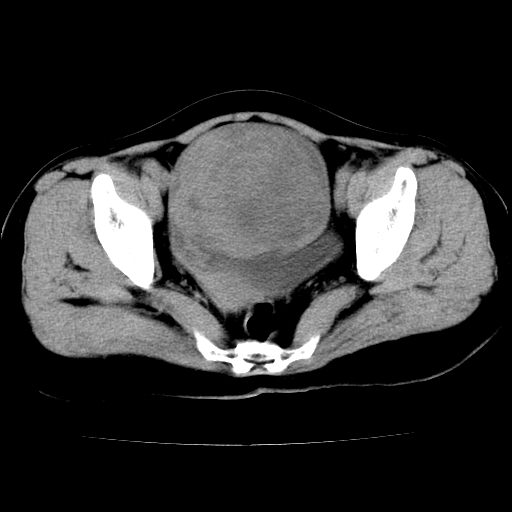

标题: CT24785:女,62岁,发现下腹部肿物半年。 [打印本页]

女,62岁,发现下腹部肿物半年,下腹部不适。

老年女性患者,盆腔囊实性占位,ct增强不均匀强化,未见壁结节,未见腹水及盆腔积液,考虑附件囊腺瘤可能性大!

考虑子宫平滑肌肉瘤可能性大。

卵巢囊腺瘤或囊腺癌可能。

考虑附件粘液性囊腺瘤可能性大。

实性成分太多,要是囊腺瘤也要考虑恶性。